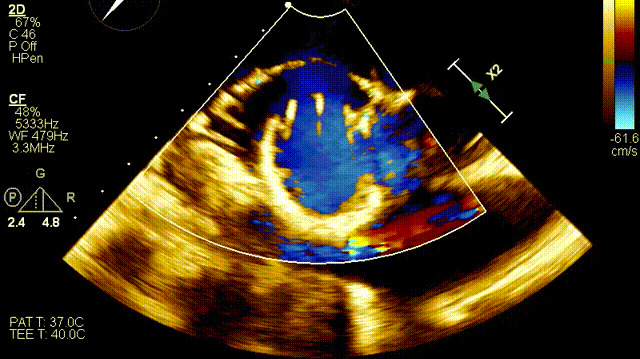

術后超聲

手術在全麻狀態下開展,此次手術采用經右側頸靜脈入路的方式將輸送器送入患者心臟內,在TEE及DSA引導下調整輸送器頭端角度,使得輸送器與三尖瓣瓣環平面垂直。在輸送器進入右心室后釋放室間隔錨定裝置,而后釋放瓣葉夾持件(2個耳片結構)成垂直狀態。在TEE及DSA確定夾持件固定至三尖瓣葉根部且位于右室側后釋放人工瓣心房側盤片。隨后調整瓣膜同軸性以及室間隔錨定件位置(貼合室間隔),前推藏針管并固定,進而釋放室間隔錨定裝置,并再次確認瓣膜位置、穩定性及同軸性,合攏輸送鞘后撤出輸送器,完成LuX-Valve Plus人工三尖瓣瓣膜的植入。